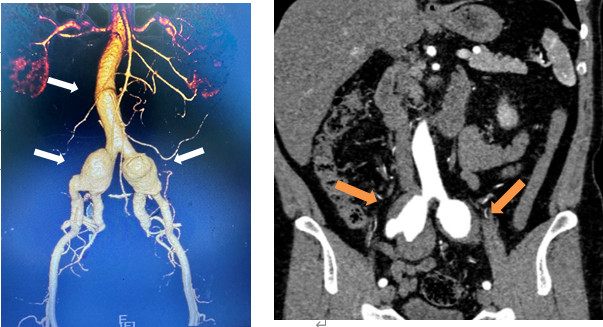

术前CTA提示腹主动脉局限性瘤样扩张及双髂动脉瘤并附壁血栓(箭头所示)。

文叔今年53岁,在一个多月前的体检中,意外查出双侧髂动脉扩张。进一步的CT检查提示:双侧髂总动脉及髂内动脉近端动脉瘤,伴附壁血栓形成。这意味着,文叔体内就像埋了随时会爆炸的炸弹:动脉瘤一旦破裂,后果不堪设想。

文叔随即来到福建省人民医院血管外科求治。检查发现,他体内一连串动脉瘤中最大的直径已超过4厘米,瘤体内有大量血栓,与输尿管、髂静脉、膀胱等重要组织紧紧粘在一起。